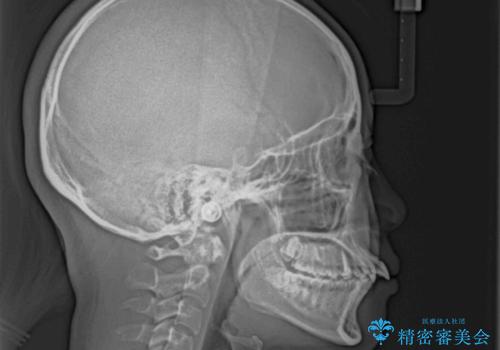

飛び出した口元を改善したい ワイヤー装置による抜歯矯正治療

- 下唇の上に乗っかってしまうくらい前歯が飛び出していることを気にして来院された患者様です。

唇を閉じようとするとオトガイ部に力が入ってしまい、うまく閉じることができない状態であったため、上下左右の第一小臼歯4本を抜歯して、ワイヤー装置にて矯正治療を行うこととしました。

飛び出した前歯はしっかりと引っ込み、横顔の印象が大きく変化しました。